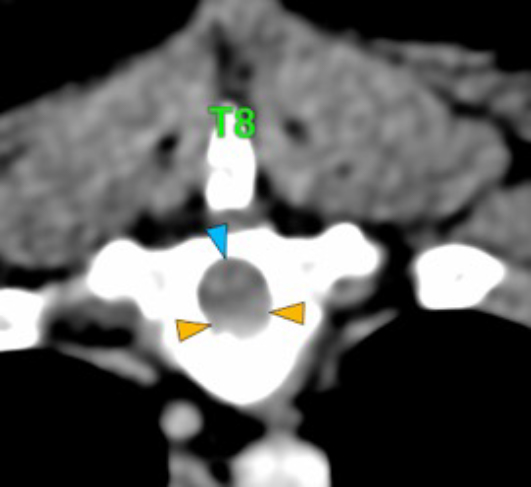

The osteolytic lesions have soft tissue attenuation that shows moderate and slightly heterogeneous post-contrast enhancement. In some of the vertebrae, the lesions cause lysis of the cortex and extend into the vertebral canal (orange arrows) causing variable degree of compression of the spinal cord and cauda equina (blue arrows). At the level of the vertebral bodies of T7, T8, T9 and T12 the lesions extend into the ventral and central aspect of the vertebral canal causing a mild compression of the spinal cord. At the level of T13, L1, L4 and L5 the lesions extend into the ventral and central aspect of the vertebral canal, causing moderate compression of the spinal cord. At the vertebral body of L6 the lesion extends into the ventral and central aspect of the vertebral canal, at the mid-aspect of L6, occupying approx. 90% of the diameter of the vertebral canal causing a severe compression of the cauda equina. At the level of L7, the lesion extends into the ventral and both lateral aspects of the vertebral canal, causing severe compression of the cauda equina.